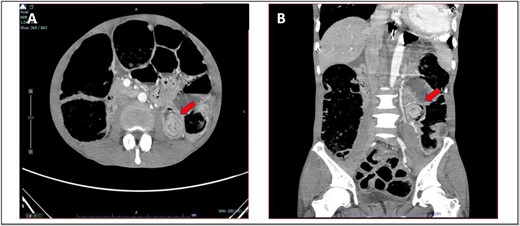

A 52-year-old Malay man, an active smoker, with underlying pulmonary hypertension secondary to atrial septal defect secundum with Eisenmenger syndrome and chronic lung disease. He had been experiencing symptoms of intestinal obstruction for a week. He had abdominal pain for 1 day, vomiting for 2 days, and unable to pass motion for the past 1 week. Patient was tachypnoeic with a respiratory rate of 35/min, a pulse rate of 116 bpm, and SPO2 of 90% under high-flow nasal cannula 50%/50 L. Abdominal radiograph showed dilated large bowel. Computed tomography abdomen and pelvis revealed short segment circumferential enhancing bowel wall thickening at rectosigmoid region causing intraluminal obstruction and presence of target sign at left lumbar region suggestive of jejunojejunal intussusception (Figs 2 and 3).

(A) Axial view and (B) coronal view of computed tomography showed presence of doughnut sign at left lumbar region suggestive of jejunojejunal intussusception (red arrow).